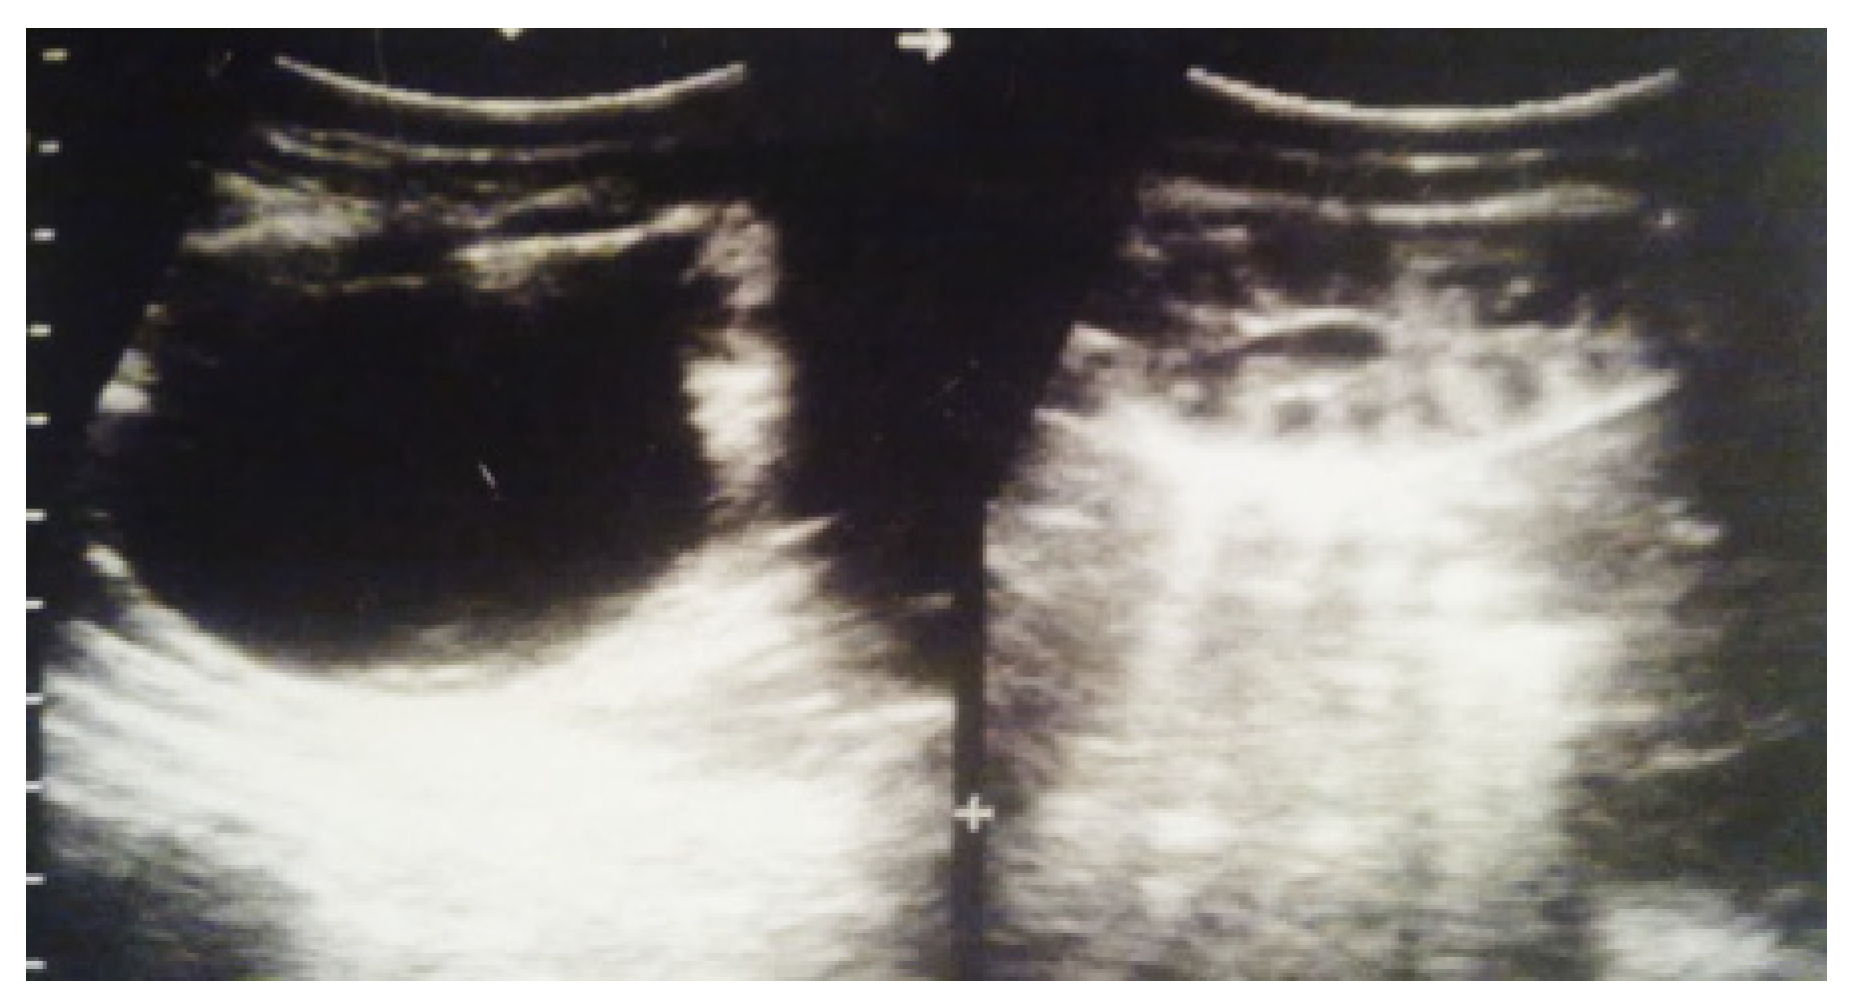

Our experience with congenital malformations of the urinary system refers to the following clinical case (Figure 2, Figure 3, Figure 4, Figure 5, Figure 6, Figure 7, Figure 8 and Figure 9). In the first case, during pregnancy, the 21-week ultrasound determined bilateral renal pyelectasia. The fetus had hydronephrosis on the right; at 31 weeks, it had bilateral hydrocalconephrosis; and at 32 weeks, bilateral pyelectasia. It suffered premature birth at 36 weeks, with complicated anomalies of the forces of contraction, prolonged birth, and birth weight of 2200 g. Postnatal ultrasonography was supplemented by intravenous urography, and bilateral hydronephrosis was determined. Hydrocalconephrosis on the left was discovered. The complete diagnosis was established: congenital renal malformation; bilateral pyelectasia; bilateral hydronephrosis; hydrocalconephrosis on the left; and severe reduced glomerular filtration rate (GFR), GFR > 2SD below mean.

Figure 2. Intrauterine ultrasound at the 21st week of pregnancy. Ultrasonography—the fetus corresponds to the age of 20–21 weeks. Bilateral renal pyelectasia.